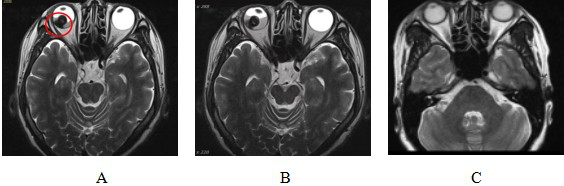

图 3 泪囊鳞癌患者CIRT治疗前后磁共振成像(MRI)及体征对比图

Figure 3 Comparison of magnetic resonance imaging (MRI) and physical signs in patients with dacryocystosquamous cell carcinoma before and after CIRT treatment

Note: Figure 3A: MRI examination before CIRT treatment showed that: the right lacrimal sac was occupied, the boundary between the eyeball, the medial rectus muscle and the inferior rectus muscle was not clear, the eyeball was compressed and displaced, and the right nasolacrimal duct was invaded. Figure 3B: Abnormal signs before CIRT treatment; Figure 3C: MRI examination after CIRT treatment showed that: the lesion disappeared, and the efficacy evaluation was CR; Figure 3D: Recovery of physical signs after CIRT treatment.